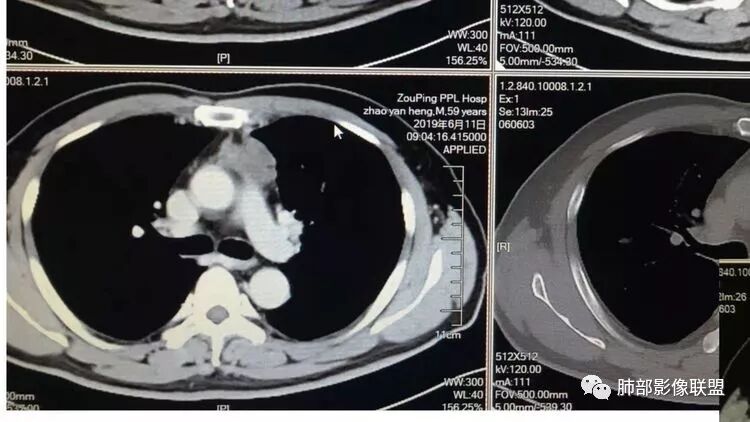

因为原病灶没看到,现在原有位置有一大病灶,如果是新发的,原有病灶会推移一边,但是没看到,倾向于原病灶增大

根据强化,高的70HU,低的没测,考虑囊实性

实性部分明显强

偏一侧

上面来的血供,病灶深分叶

附近心包似乎也不干净

有淋巴结

从前后变化,病灶的形态、强化、附近的淋巴结、心包改变,支持恶性

这图看起来有结节感